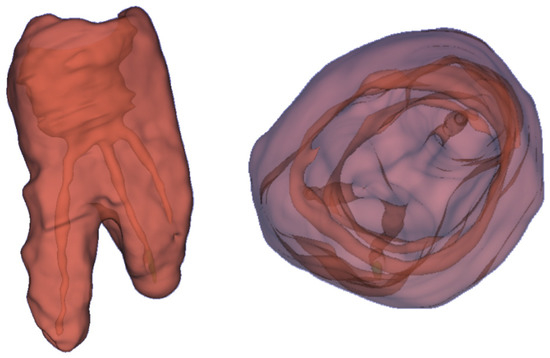

Various types of software and hardware tools are required to develop and visualize holographic 3D models. In terms of hardware, the system is designed to run on Microsoft HoloLens 2. The structural models of teeth and root canals are reconstructed by a developed Python application and the models are exported into Unreal Engine (Epic Games, Potomac, MD, USA). To create the holographic 3D models of patients’ teeth, which are presented in Figure 5, DICOM RAW data from CT scans were used. By applying semi-automated algorithms, the CT scan is segmented. Every elementary volume component (i.e., voxels or Hounsfield units) of the CT scan is labeled manually and then processed. Here, the fill-between-slices algorithm was used. The application, which enables the creation of 3D holograms, was written in Python, see Figure 6. In the first step, a CT scan (DICOM data) was loaded. Next, each layer was reviewed to obtain the required range of minimal and maximal values for the entire CT scan. The values obtained are applied to select the appropriate range to obtain the best quality model. For example, the range of 0–50,000, where 0 denotes a black color and 50,000 white colors. The created range selection enables us to decide which pixels should be skipped in the generated model. It can be compared to printing black pictures on white paper. The printer is only placing black ink in black spots on white paper and skips everything where it should print in white color. Creating 3D models is the same situation. We decide which color values from the DICOM pictures should be used for creating the model and which are skipped as empty spaces.

Figure 5. The 3D holograms of the tooth, with visible root canals.